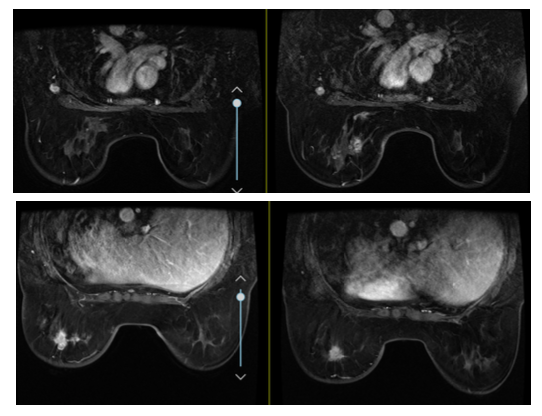

2018年10月30日复查乳腺MRI(图2):左乳乳腺癌复查,较前(2018年7月10日)部分肿块略饱满。双侧腋下淋巴结肿大,较前相仿。双乳小叶增生,右乳多发小结节灶,BI-RADS 3,较前相仿。

图2 第一次进展 2018年10月30日(均为右图)MRI对比2018年7月10日(均为左图)乳腺MRI